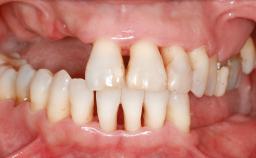

Staged bone augmentation of the alveolar ridge is indicated whenever a proposed implant site is deficient and will not support implant placement with simultaneous grafting. This is particularly true of healed sites presenting with facial flattening of the ridge. Since primary stability cannot possibly be achieved in this situation, it is recommended to use a staged approach with guided bone regeneration (GBR) for correct three-dimensional placement of the implant. In the anterior maxilla, staged GBR procedures are conducted not only to provide adequate bone volume for implant placement but also to restore a proper and stable contour of the orofacial ridge for improved long-term esthetics. A case is presented that demonstrates the technique for single-tooth replacement utilizing a staged approach with a particulate grafting material. A 50-year-old man whose tooth 11 was missing presented for consultation to the Center for Implant Dentistry in January 2010.

Soft Tissue Anatomy Intact Defective

Bone Volume Horizontally and vertically sufficient Horizontally deficient Deficient vertically or deficient vertically AND horizontally